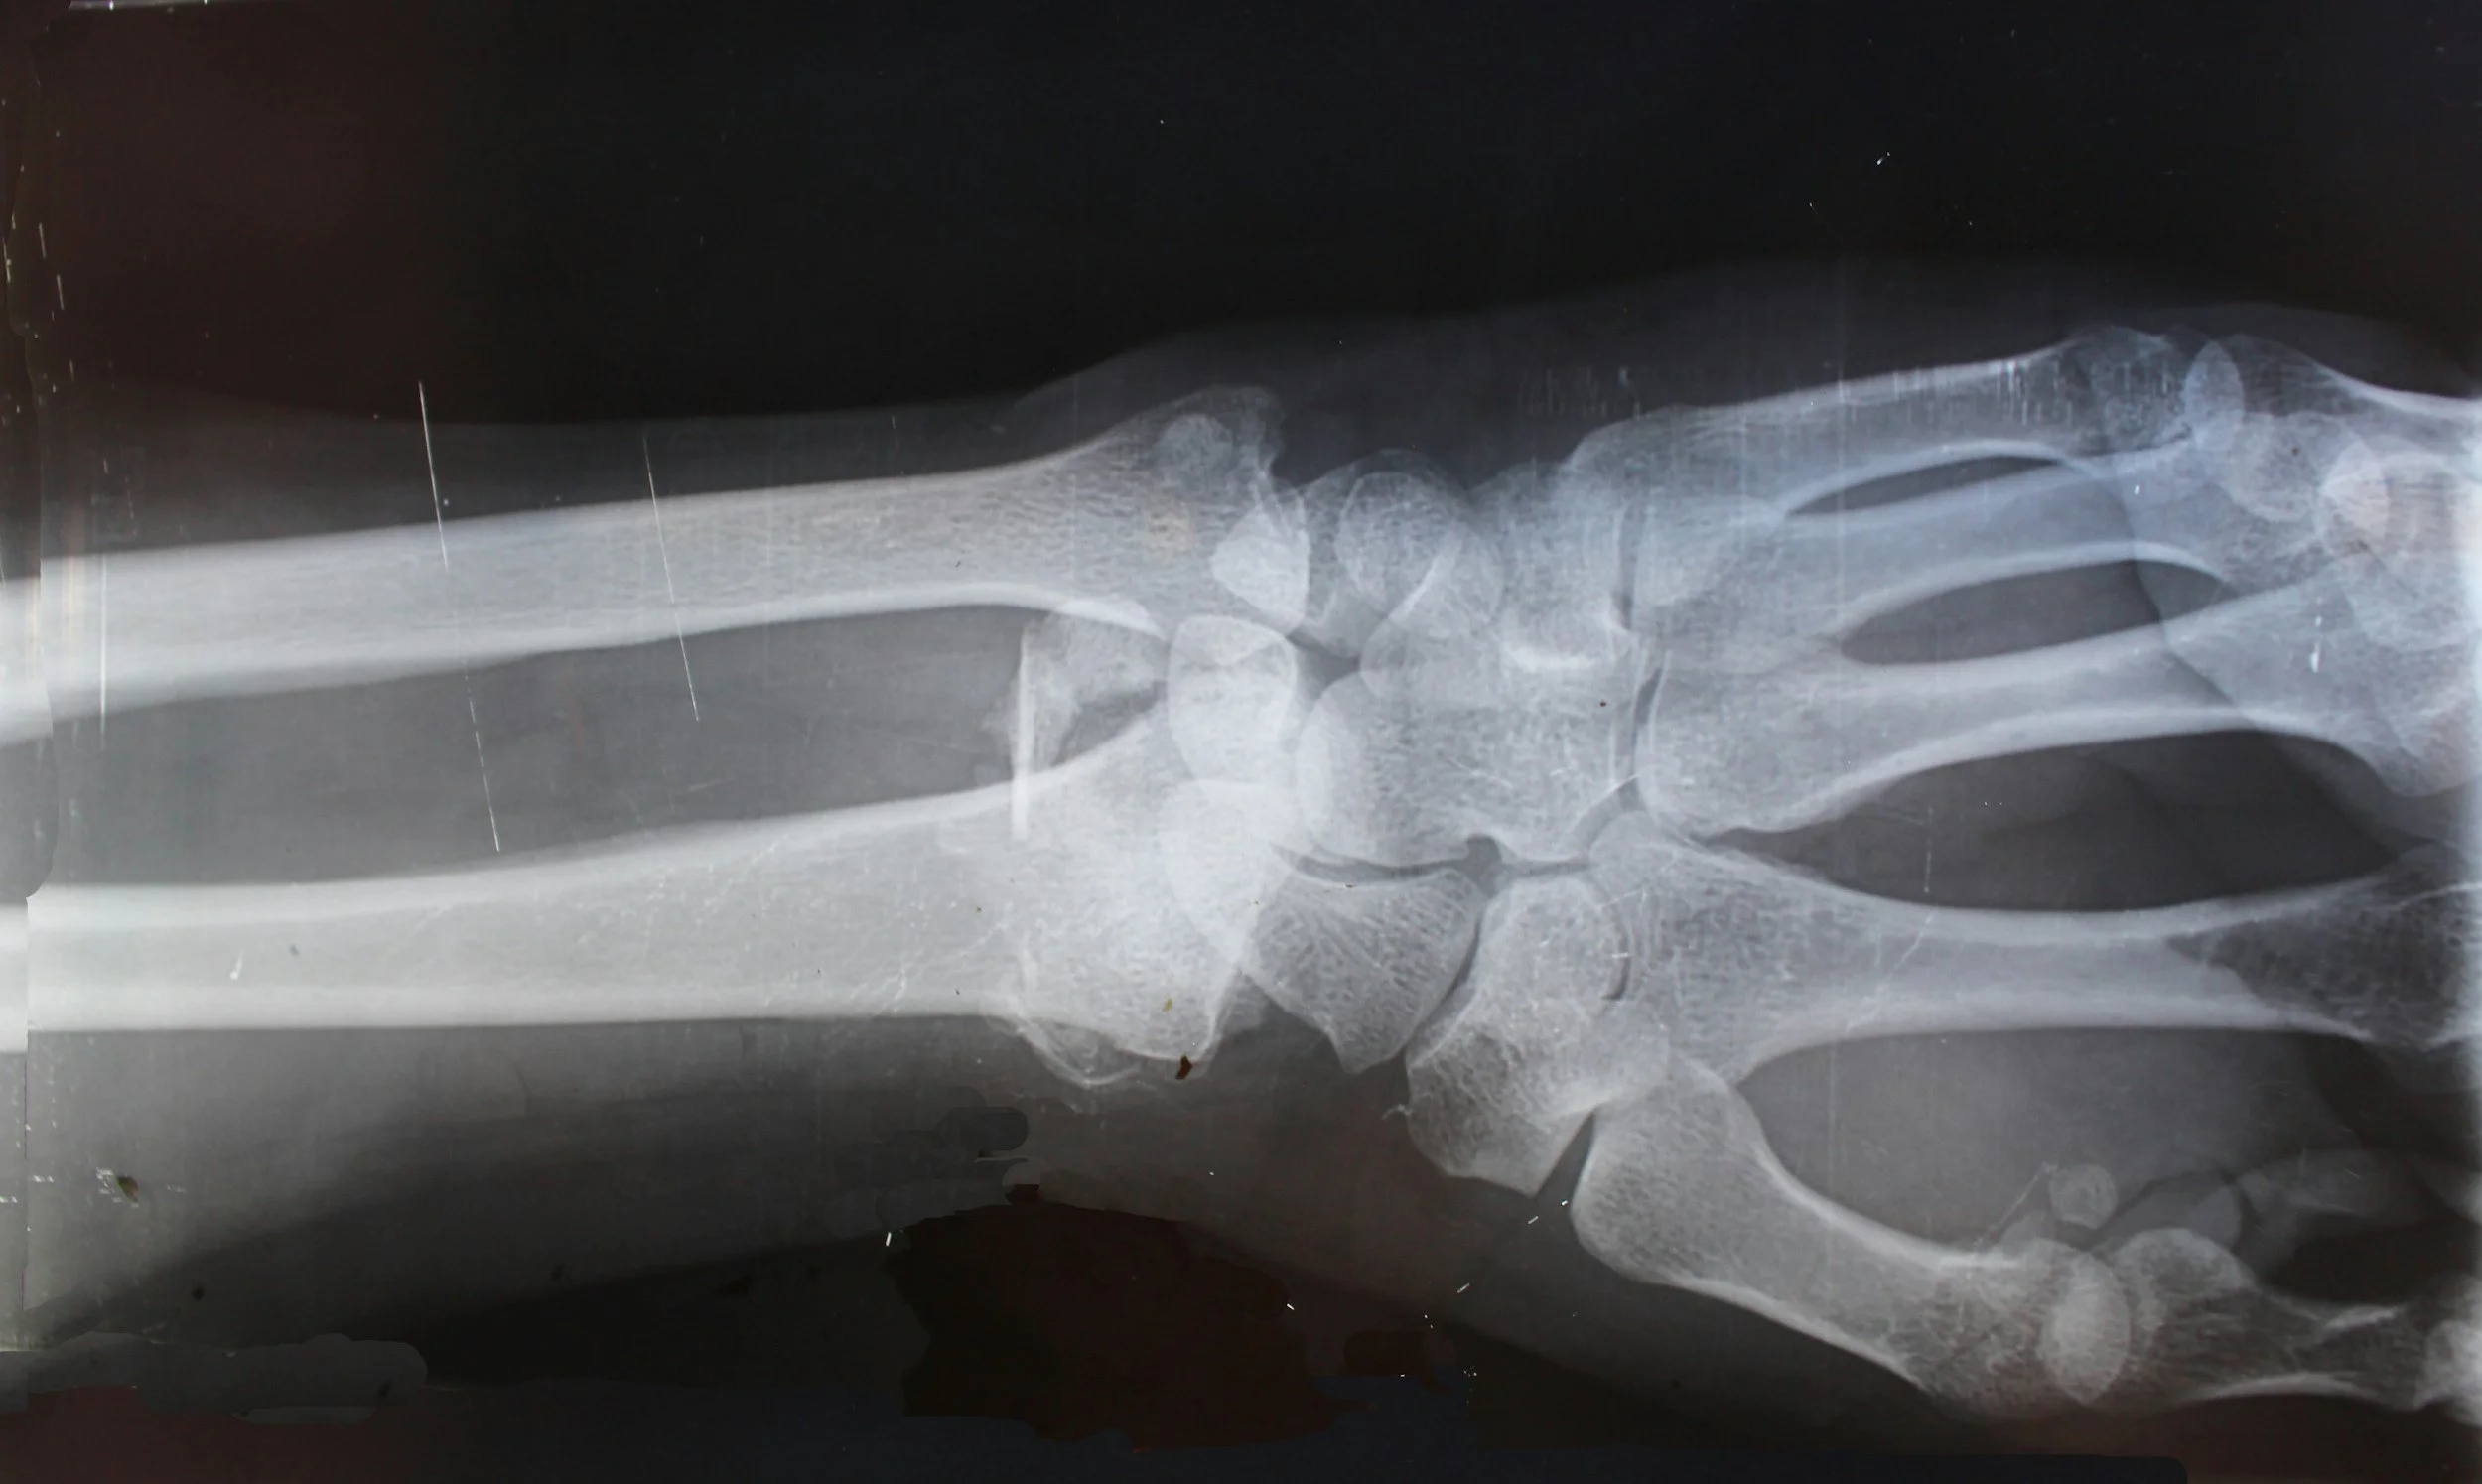

Client information sheets What is physiotherapy and what your child can expect in their appointment What is an x-ray and what should your child expect information sheet? Child rights in healthcare